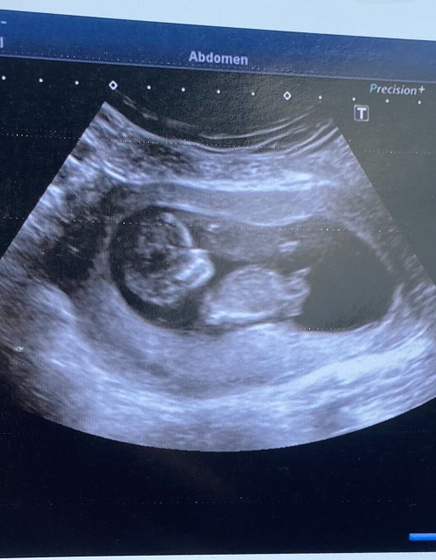

Знаю, есть тут такие специалисты, которые могут по фото предположить пол)) ? сегодня на скрининге спросила врача, говорит «приходите в 20 недель, тогда скажу»(

хотя многим на этом сроке уже хотя бы предположить могут пол… на кого похож?)

У вас торчит)) у меня пост есть, посмотрите как девочка выглядит))) там бугорок параллельно спинке идет. Мне сказали, что у меня девчуля. Так что у вас вероятно мальчишка

Мальчик

На мальчика